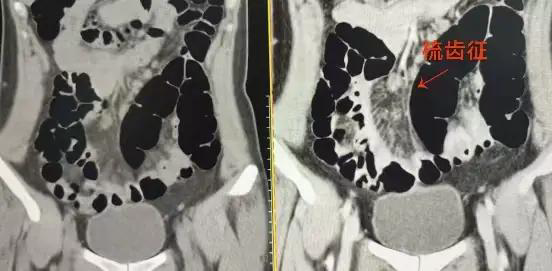

△增强前 △增强后

从图像可以看见,增强前患者的结肠充气明显,增强后,原本看不见的炎症区域变得清晰可见。在回肠的最后一段,因为炎症和周围组织的改变,系膜(就是连接肠道和身体的薄膜)呈现出一种像梳齿一样的排列,即梳齿样改变。这一准确的影像学表现为医生提供了诊断克罗恩病的重要“线索”。